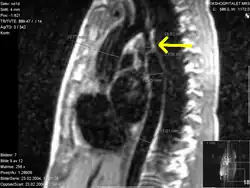

Koarktation der Aorta mit verschiedenen bildgebenden Verfahren:

A – Enge Koarktation am Aortenisthmus (Pfeil)